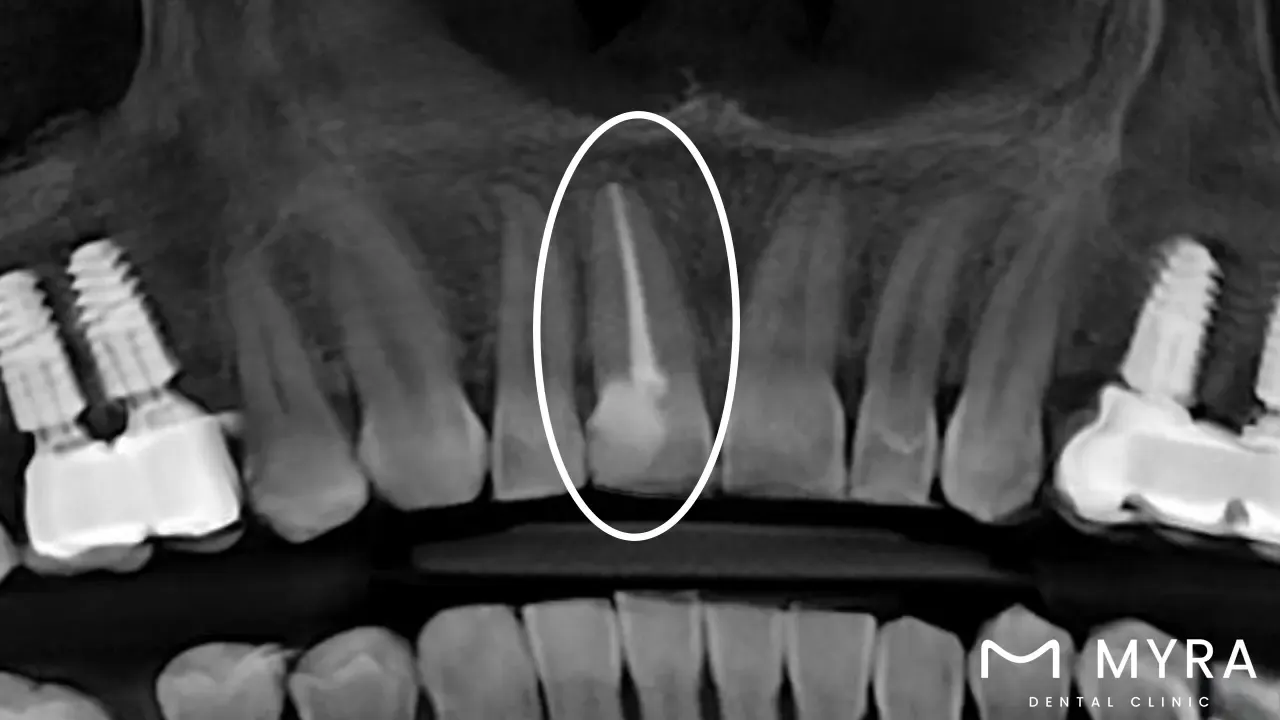

A dental root canal is usually advised when a tooth has significant decay, a damaged or fractured structure, or a big filling that has caused extensive damage to the tooth's pulp. The surgery is required if the tooth has been traumatised owing to an injury. Dentists examine and take X-rays of the tooth to evaluate its health and determine whether a root canal is the best course of action.

Dental Examination: The dentist performs a thorough dental exam, which includes X-rays, to determine the health of the problematic tooth and its surrounding tissues. The evaluation determines the amount of infection or damage and allows the dentist to design the root canal operation accordingly.

The dentist performs a thorough examination, including X-rays, at the initial visit to evaluate the impacted tooth's state and ascertain the infection's severity or damage. The dentist gives the patient local anaesthetic to numb the area and ensure their comfort throughout the process. The infected or damaged pulp next be removed, and the root canals are cleaned after the dentist makes an access hole in the tooth.

A dentist first does a thorough examination, which includes X-rays, to evaluate the condition of the problematic tooth and determine whether root canal therapy is required. The dentist goes over the course of the procedure during the stage, answers any questions, and considers other solutions if necessary.